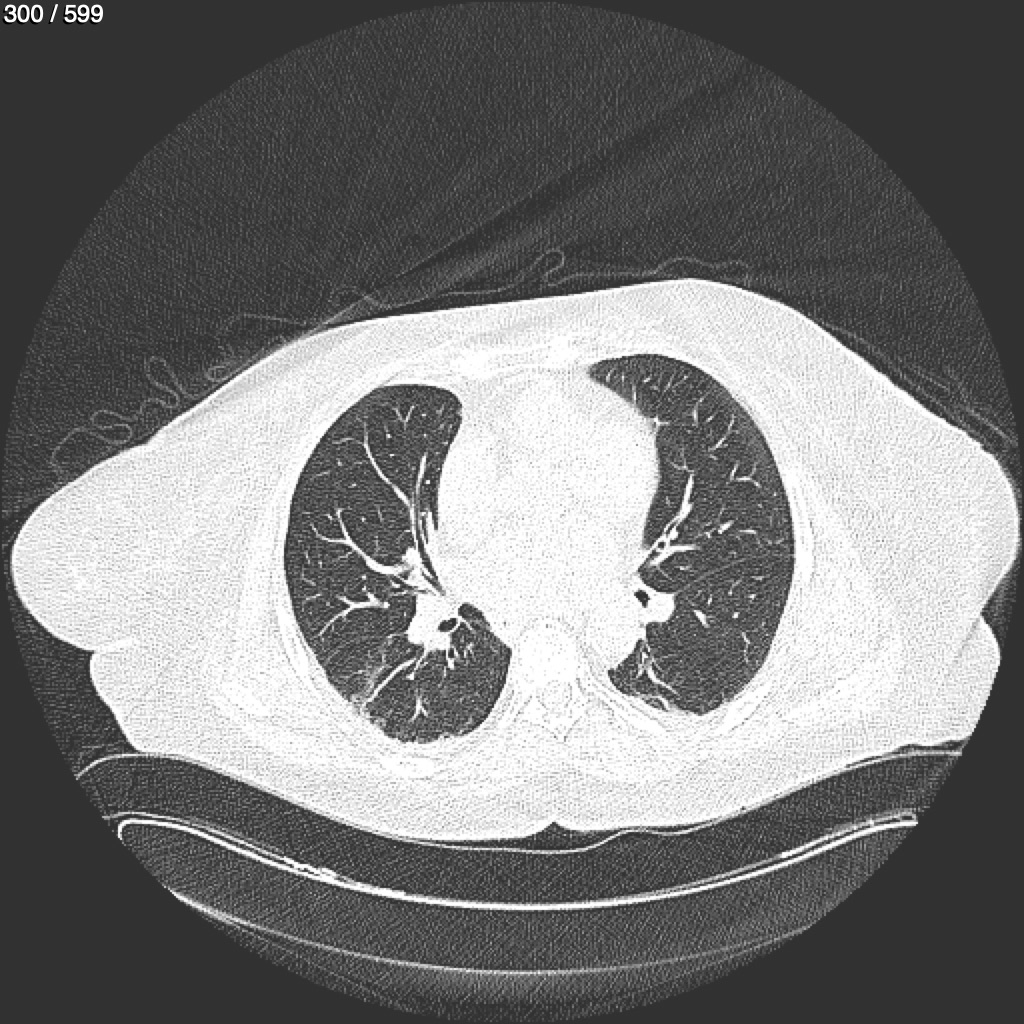

Home G​l​o​r​i​a​ ​G​l​a​d​y​s​ ​B​e​a​s​l​e​y​ ​-​ ​T​ó​r​a​x​ ​T​o​r​a​x​_​S​i​m​p​l​e​ ​(​A​d​u​l​t​o​)